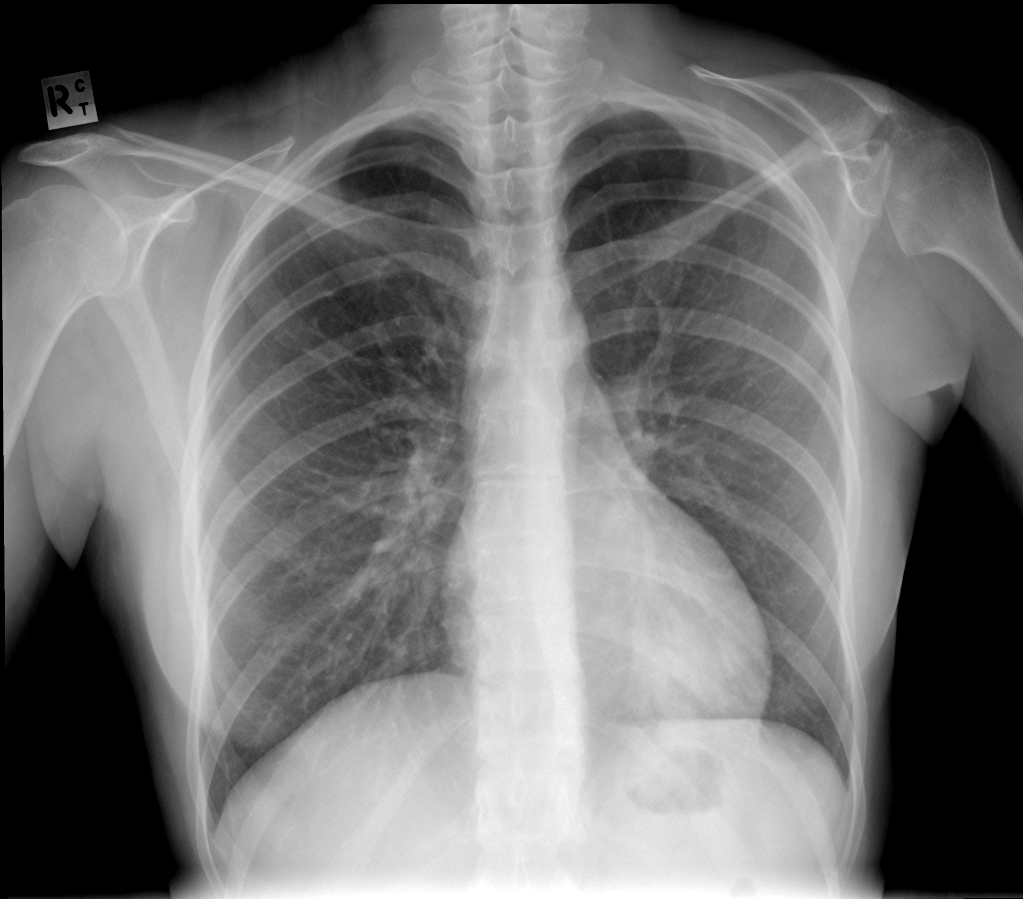

Sprengel Deformity

• Congenital elevation of the scapula

• Key associations - Klippel-Feil, omnovertebral bar

• Case courtesy of Paul Simkin, Radiopaedia.org, rID: 25311 (sprengel)